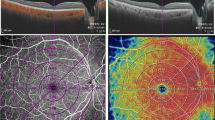

In order to quantify microvascular structure, first, the image encompassing large vessels was separated from the 3 × 3 mm image of SCP layer. Automated algorithm was applied considering thickness and intensity of large vessel. We empirically defined diameter of large vessel as 7 × 7 pixel on enface image. Then, we separated the major vessels on high intensity over 0.80 considering decorrelation signal of OCTA. Vessel threshold was defined by a multiple of maximum intensity of pixel and constant range from 0.65 to 0.90, according to the consensus of two physicians. Median filter was applied, in order to exclude small vessels and high intensity signal noise. Finally, large vessels were masked out to generate the capillary image. The perfusion density was calculated on binarized images, using an Image J (National Institutes of Health [NIH], Bethesda, MD, USA) ‘mean threshold’ algorithm. Binary images were then converted into skeletonized images, where vessels were reduced to a width of one pixel. Skeletonized images were used to calculate VLD using Image J program. Figure 4 represents imaging process of en face binarized and skeletonized images from the SCP and DCP layers. Secondly, NPA was measured based on a total retinal slab of 12 × 12 mm SS-OCTA image and semi-automatically quantified using MATLAB software (R2013b, MathWorks, Inc., Natick, MA, USA). In the context of the current study, NPA was defined as a contiguous region without microvasculature, composed of rectangular 17 × 17 (289) pixels (≥ 0.04 mm2). Area threshold was defined as 250 pixels. The threshold value to binarize the NPA was based on the method previously described by Kim et al.28 (250 pixels on the same SS-OCTA instrument). Fovea and optic disc area were manually excluded and finally NPA was calculated (Fig. 5).

source OCTA images. (A) Superficial capillary plexus of 3 × 3 mm angio en face images. The foveal avascular zone area was manually outlined. (B) Separated large vessels image is subtracted from original OCTA images. (C,D) Binary images used to calculate perfusion density of superficial and deep capillary plexus layer. (E,F) Skeletonized images of corresponding binary images used to calculate vessel length density of superficial and deep capillary plexus layer.

Imaging process for the quantification of microvascular parameters from swept-